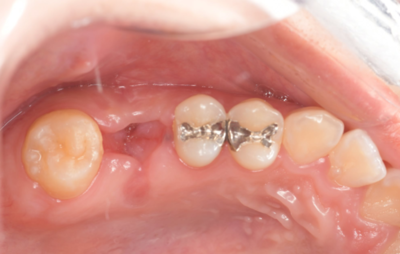

初診時口腔内写真

初診時パノラマX線写真と口腔内写真。

右上6に腫脹と排膿がみられた。